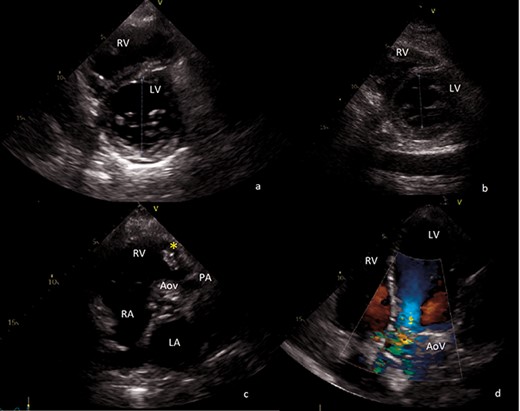

Severe aortic valve regurgitation with multiple vegetations, the largest of about 11 mm length, protruding to the aorta as well as to the left ventricle outflow tract (Fig. 1d).

Transthoracic echocardiography images. (a) Preoperative short axis view of left ventricle. End-diastolic left ventricle diameter of 68 mm. (b) Postoperative short axis view of left ventricle. End-diastolic left ventricle diameter of 43 mm. (c) Sizable vegetation (yellow asterisk) of about 4 cm provoking right ventricular outflow obstruction. (d) Four-chamber view, showing severe aortic regurgitation. AoV aortic valve; LA left atrium; LV left ventricle; PA pulmonary artery; RA right atrium; RV right ventricle.